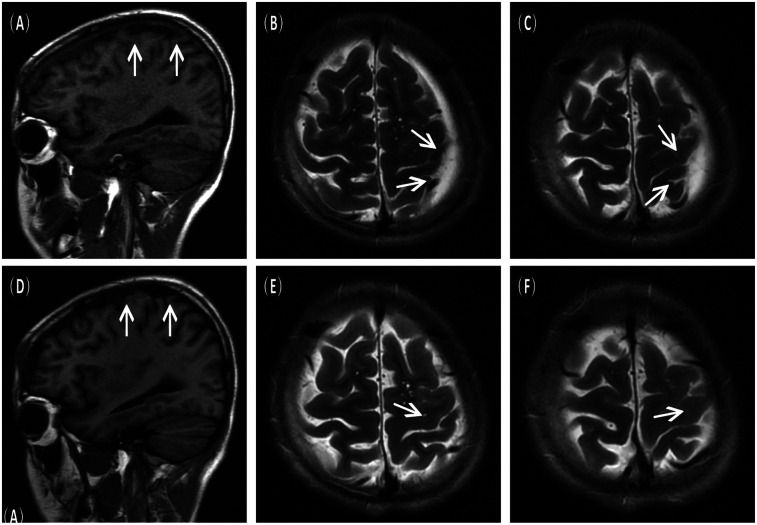

This case report discusses a 16-year-old male with a previously diagnosed left fronto-temporo-parietal arachnoid cyst (AC) who developed progressively worsening intermittent headaches. Magnetic resonance imaging (MRI) revealed a spontaneous chronic subdural hematoma (CSDH), despite no history of trauma or bleeding disorders. The cyst, discovered incidentally three years prior, had been asymptomatic until this event; hence, no interval cranial computed tomography (CT) or MR imaging was performed. The patient underwent burr-hole irrigation and drainage under general anaesthesia. Postoperative scans confirmed complete resolution of the hematoma and a significant reduction in the cyst size, with no recurrence of the cyst at the six-month follow-up. This case, supported by a systematic review of 28 recent studies (2020-2025), highlights that AC can spontaneously rupture, leading to CSDH. Burr-hole irrigation surgery proves to be a safe and efficient intervention, emphasizing the need for long-term monitoring in AC patients to manage potential hemorrhagic complications promptly.

Abstract Image